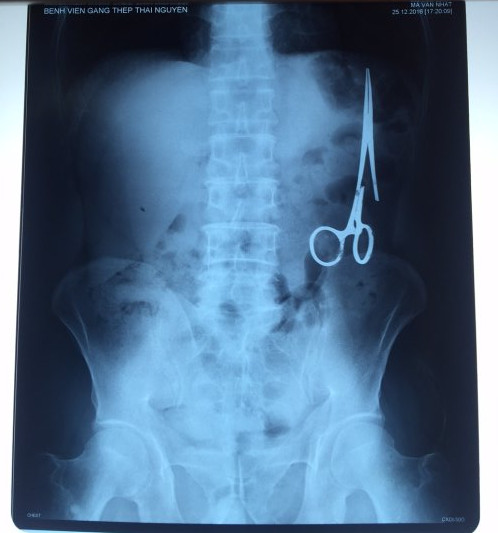

遺留在病人腹中的剪刀

據(jù)越南青年報(bào)1月2日報(bào)道,在越南首都河內(nèi)醫(yī)療專家的幫助下,越南東北部的太原?。═hai Nguyen)鑄鋼醫(yī)院的醫(yī)生日前從54歲患者M(jìn).V.N腹中取出一把醫(yī)用剪刀。這把剪刀是此前曾為M.V.N手術(shù)的醫(yī)生遺留的,已經(jīng)在其腹中待了18年時(shí)間。

醫(yī)務(wù)人員表示,這把剪刀遺留在病人腹部左側(cè),與結(jié)腸緊挨著。剪刀的把手已經(jīng)生銹,部分器官也已經(jīng)與剪刀粘連起來。但在過去多年中,M.V.N沒有任何不適感覺,也從未因?yàn)榱粼诟怪械募舻兑l(fā)的相關(guān)問題去看過醫(yī)生。直到2016年12月,M.V.N因?yàn)樵庥隽艘粓鲕嚨湥诺借T鋼醫(yī)院進(jìn)行身體檢查。

超聲波檢查顯示,M.V.N的腸子中有個(gè)奇怪物體,看起來就像醫(yī)用剪刀。M.V.N證實(shí),他曾于1998年6月份在北江省綜合醫(yī)院接受手術(shù),在此后也從未進(jìn)行過任何手術(shù)。近來,他感到腹部有些疼痛,并試圖通過服用藥物治療。12月27日,M.V.N回到北江省綜合醫(yī)院再次進(jìn)行超聲波檢查,顯示其腹部的確存在怪異物體。